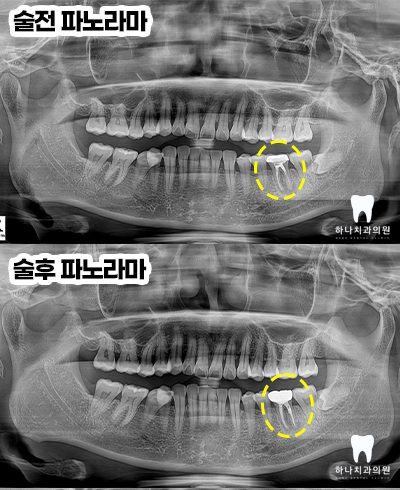

위 환자분께서는 40대 여성분으로

울산삼산동치과 하나치과

홈페이지 블로그를 통해 재신경치료

성공 케이스를 보시고 멀리 북구에서

내원해 주셨습니다.

타 치과에서는 발치를 권유받으셨다고

말씀해 주셨다고 하시며 재신경치료를

받아볼 수 있냐고 여쭤보셨는데요.

우선 치아의 동요도가 없고

염증의 형태가 치근단에 집중되어 있어서

재신경치료를 시도해 보자고 말씀드린 후

진행하기로 하였습니다.

우선 CT 촬영 후 사진에서 보았을 때

4회에 걸쳐진 치료를 완료하고

근관의 완전한 확보, 세척, 충전을

완료한 뒤 마무리 후 본뜨기 전의 모습입니다.

앞으로 2년 이상의 염증 부분의

잇몸뼈 리모델링 기간을 거쳐야

성공했음을 확신할 수 있다고